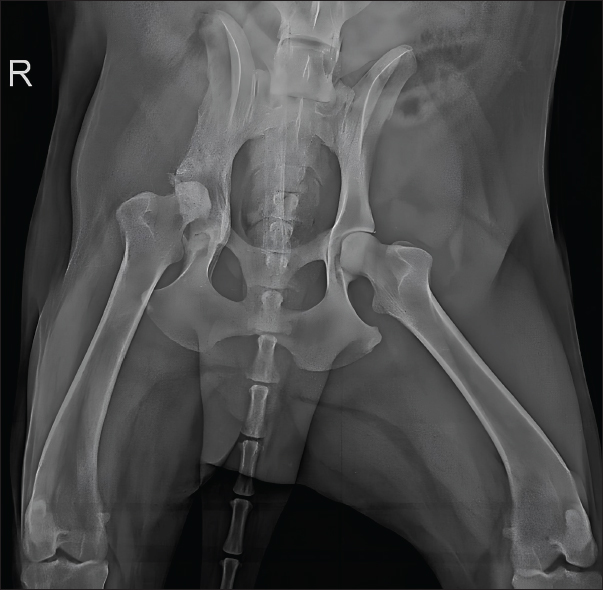

The dog showed significant clinical improvement, including reduced lameness and restored appetite, after 30 days of therapy. Pelvic radiographs revealed slight regression of periosteal proliferation and osteolytic areas (Fig. 4). Hematology and serum biochemistry remained within normal limits.

Fig. 4. Radiographic examination of the dog 30 days after initiation of itraconazole treatment, showing slight regression of periosteal bone proliferation and reduction of osteolytic areas.